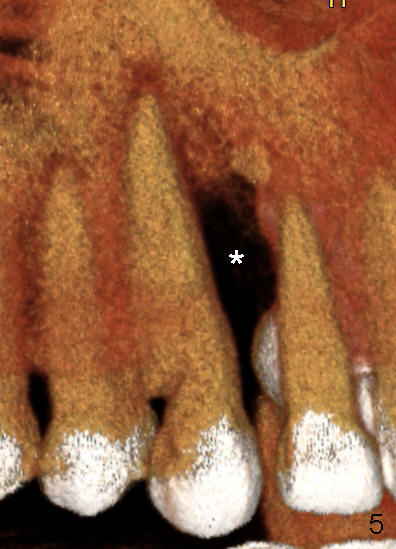

A male patient had trauma to the tooth #6 at the age of 13.  The affected tooth has remained asymptomatic for more than 30 years (Fig.1).   X-ray reveals an oblique root fracture (Fig.2 >) with radiolucency in the mesial alveolus (*, apparently normal trabecular pattern).  Six years later (Feb. 2011), an acute infection develops (Fig.4 *).  It requires incision & draining and antibiotic.  At that time, the trabecular pattern disappears around the fracture line mesially (Fig.3 *).  Four months later cone beam CT shows bone loss between #6 and 7 (Fig.5 *).  Root canal therapy is done as a palliative measure (Fig.6 R; C: Cavit).  Three months later, MTA (mineral trioxide aggregate) is placed in the coronal canal next to the fracture line (Fig.7 M).  It is hoped that MTA can promote nearby bone and cementum to regenerate to seal the fracture line.  Four months after MTA application, there is no sign of bone regeneration (Fig.8).  Bone is lost for approximately 7 mm.